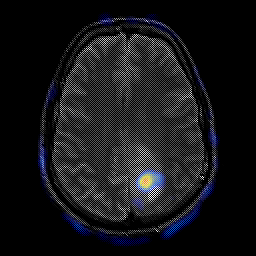

glioma overlay -- Slice #19

[Home][Help][Clinical] Slice 19